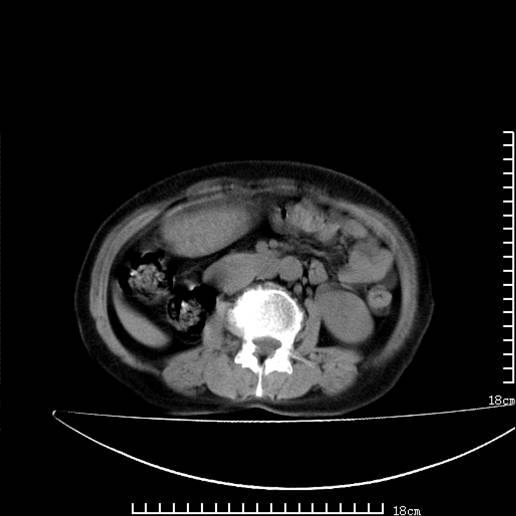

以下是引用pujunzhi在2008-5-30 15:31:00的发言:[br]异位肾—盆腔肾。当看到肾窝无肾脏时,要想到孤立肾和异位肾,异位肾最常见是盆腔肾,偶见胸腔,易误认为肺占位,只要想到就不会漏诊。建议增强扫描。